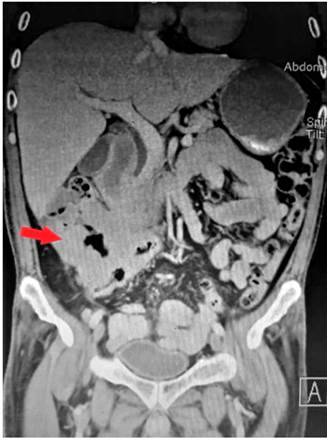

La ecografía abdominal reportó que a nivel del flanco derecho se observa un asa intestinal de paredes engrosadas irregulares de aspecto tumoral de 79 x 78 mm con ecografía Doppler e incremento de la vascularización. En la tomografía axial computarizada (TAC) de abdomen y pelvis se observa un engrosamiento difuso de las paredes del ángulo hepático hasta el colon ascendente y ciego con alteración de la grasa pericecal, y cambios inflamatorios en el íleon terminal, por lo que se debe descartar lesión primaria en el ciego (Figuras 1 y 2). Se realizó un estudio endoscópico digestivo alto en el que se observó una pangastropatía atrófica; la colonoscopia reveló que en todo el colon se observó alteración del patrón vascular, eritema, granular, edematosa, friable, a nivel del ángulo hepático una estenosis de aspecto maligno que impide el paso del equipo con un reporte colonoscópico de pancolitis activa con un puntaje de Mayo 2 para colitis ulcerativa. Se tomó una biopsia de la estenosis y de todos los segmentos y se reportó infiltrado inflamatorio grave de linfocitos y células plasmáticas, neutrófilos en la lámina propia, neutrófilos en el epitelio, daño epitelial, daño en las criptas de la superficie, criptitis, absceso críptico agregados linfoides, ulceración superficial y profunda, y pérdida de algunas células caliciformes sugestivos de colitis ulcerativa; y en el resto de los segmentos no se observaron granulomas sugestivos de colitis ulcerativa.